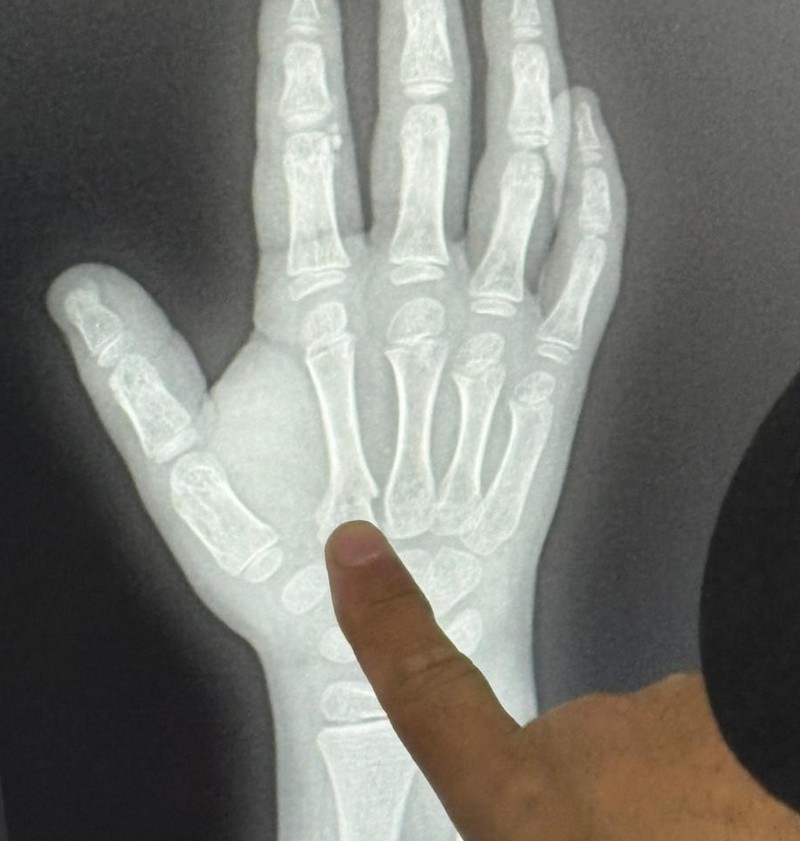

Девочка получила крайне тяжелые травмы: были сломаны челюсть, кости ладони левой руки, повреждены ребра, пострадали легкие, выбиты зубы, по всему телу - открытые раны.